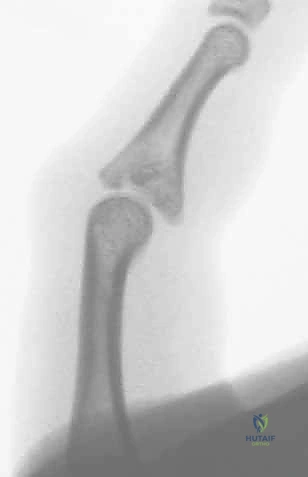

- الخلع الظهري مع كسر (Dorsal Fracture-Dislocation): وهو النوع الأكثر شيوعًا. يحدث عندما تندفع السلامية الوسطى للخلف (نحو ظهر اليد). يترافق عادة مع تمزق الصفيحة الراحية وكسر في الجزء الراحي (السفلي) من قاعدة السلامية الوسطى.

- الخلع الراحي مع كسر (Volar Fracture-Dislocation): أقل شيوعًا ولكنه أكثر تعقيدًا في العلاج. تندفع فيه السلامية الوسطى للأمام (نحو باطن اليد). يترافق مع تمزق الوتر المركزي الباسط وكسر في الجزء الظهري من المفصل.

* الوضعية الجانبية الحقيقية (True Lateral): هي الصورة الأهم على الإطلاق. من خلالها يتم تحديد حجم القطعة العظمية المكسورة، ومقدار انزياح المفصل. يبحث الجراح الماهر هنا عن علامة "V-Sign" الشهيرة، والتي تدل على عدم تطابق الأسطح المفصلية ووجود خلع جزئي غير مستقر.